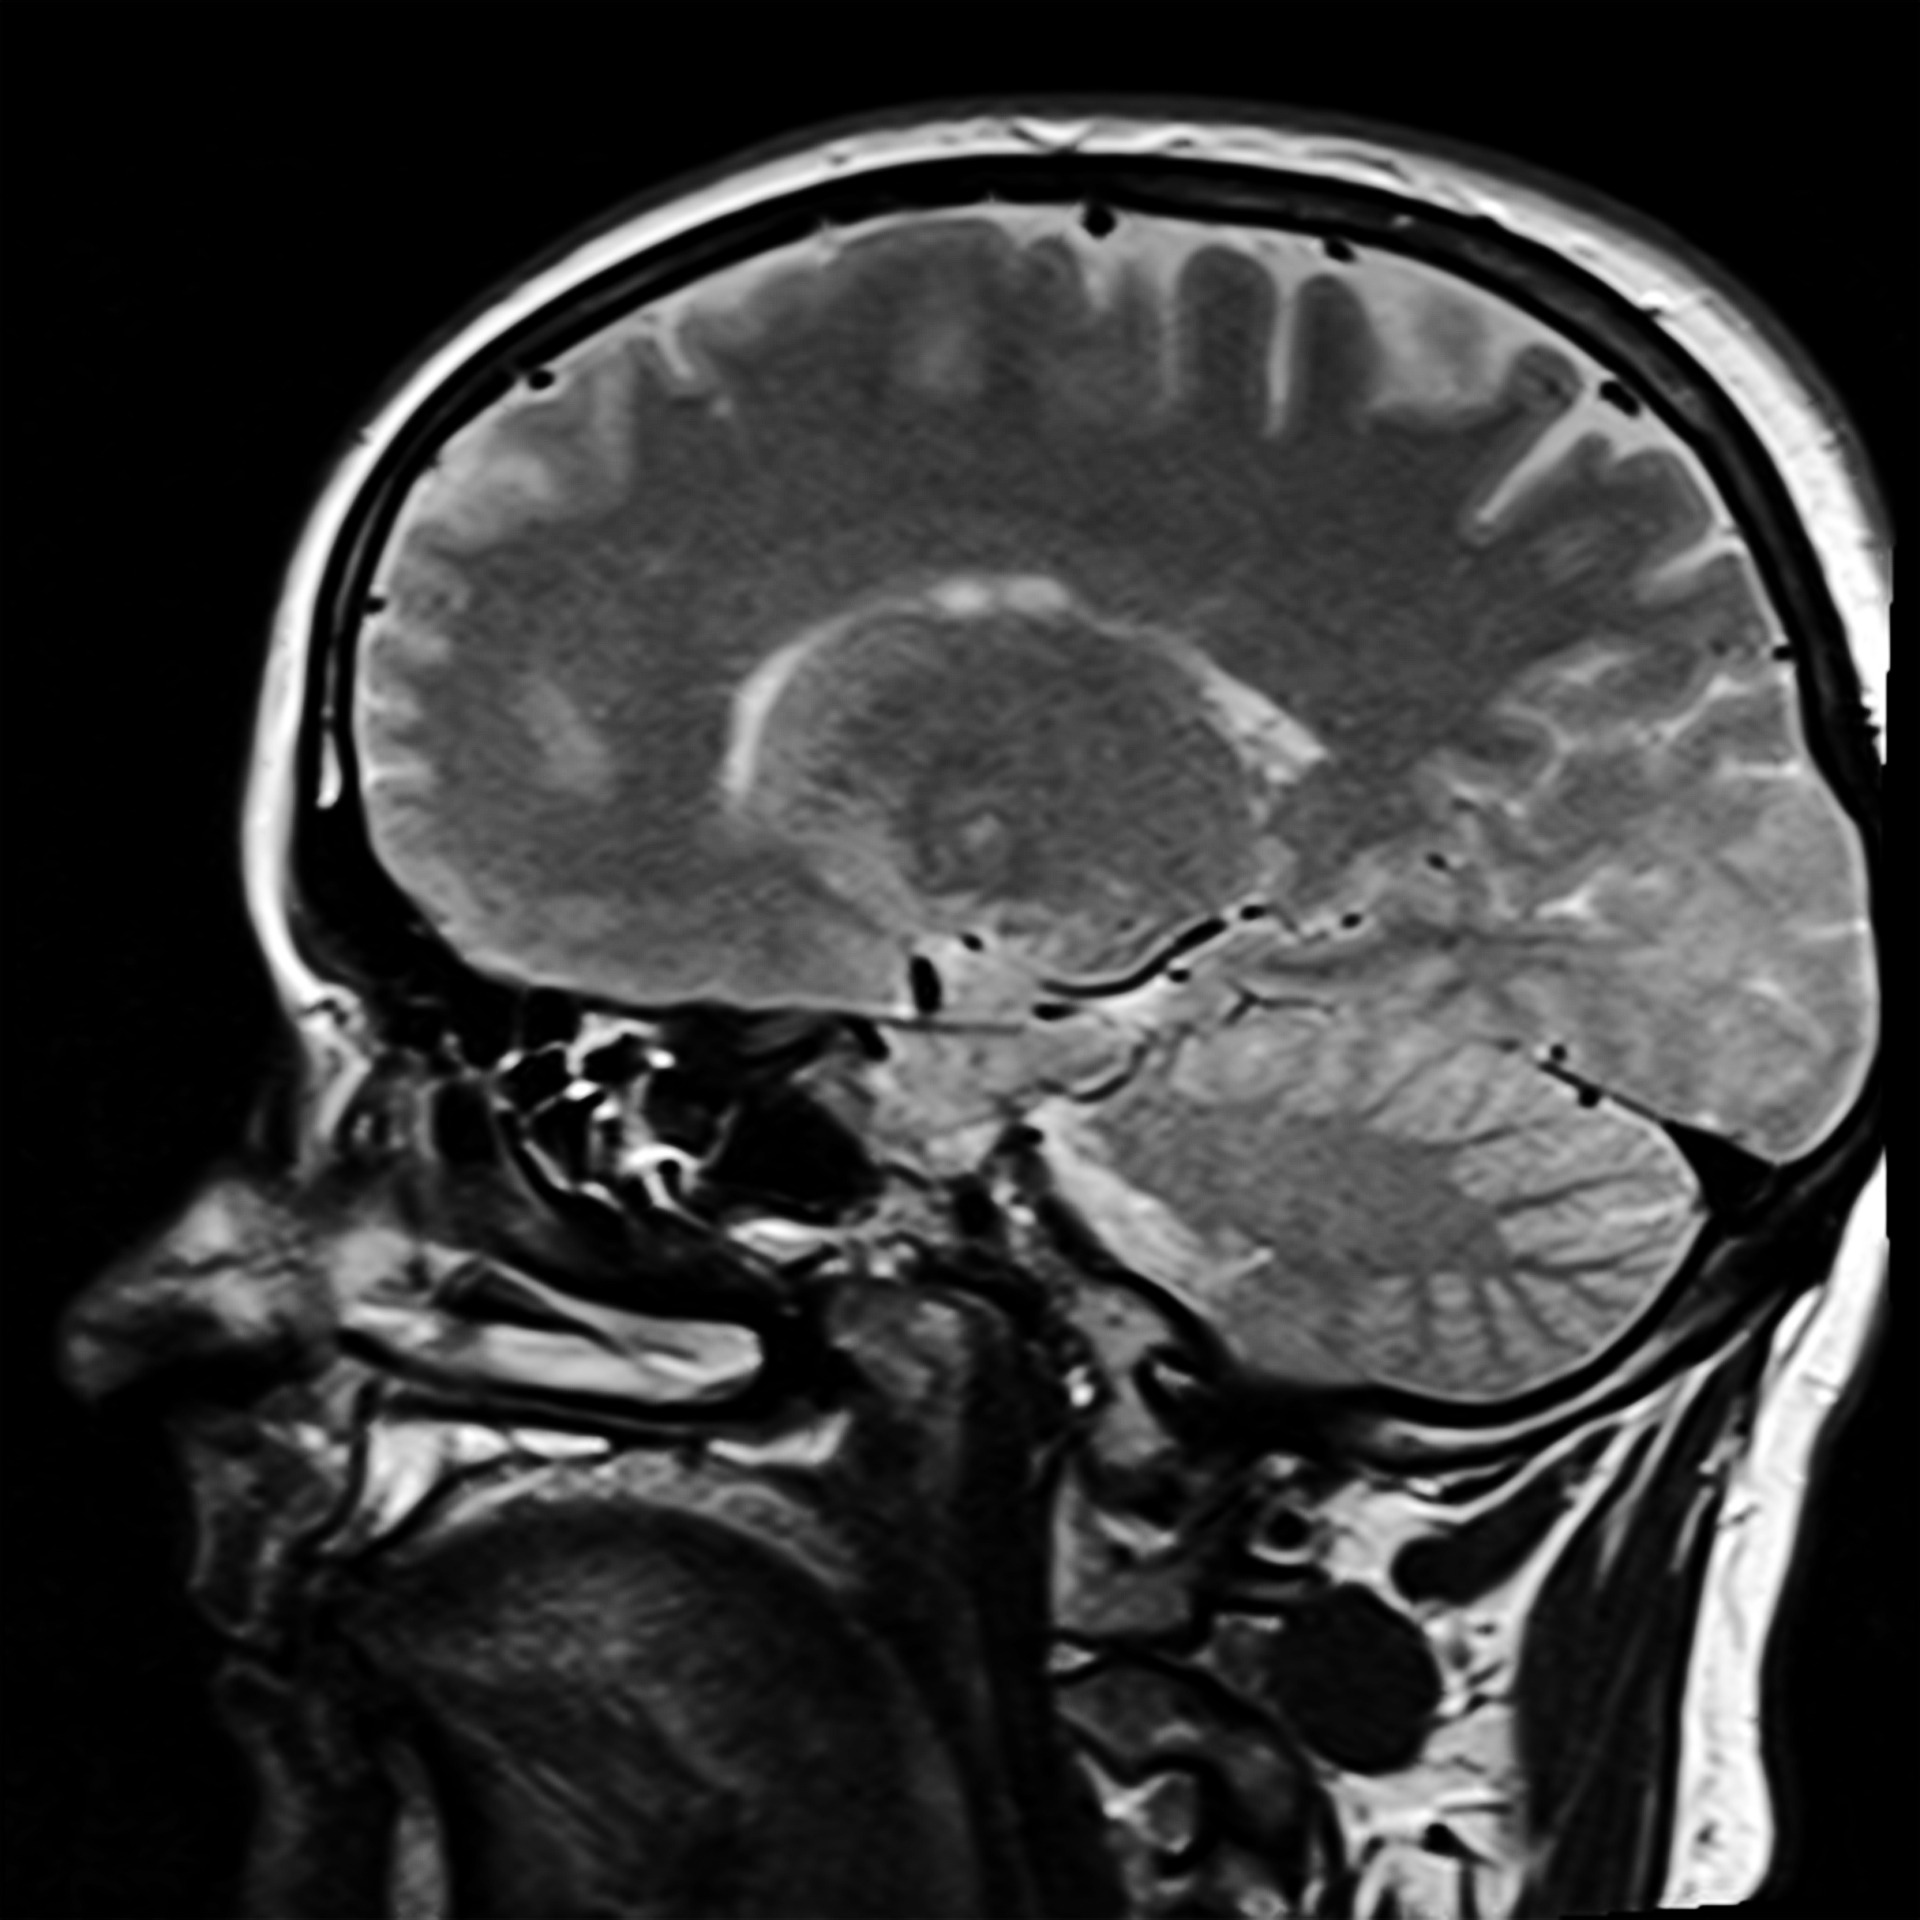

胶质母细胞瘤 (GBM)是常见的原发性恶性颅内肿瘤,占原发性脑肿瘤的16%。这是一种快速生长的侵袭性神经胶质瘤,由大脑中的神经胶质细胞发展而来。总体预后较差,即使采用...

在术中,神经外科医生使用各种技术来区分肿瘤组织和功能性脑组织,例如利用神经导航、磁共振成像(MRI)、超声波或荧光的图像引导,和术中刺激绘图。Schneider等人在他们对31名GBM患者...